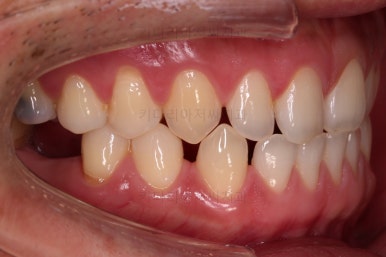

초진 시의 입안 모습입니다.

어금니가 빠져서 결손치아가 있고 치아 사이에 틈새도 있어서 교정치료도 함께 원한다고 내원해 주셨어요.

사진에서 보시는 바와 같이 윗니 1개, 아랫니 1개의 결손 부위가 보입니다.

윗니 어금니 중에는 신경치료를 마무리 못하고 임시재료로 메꿔뒀던 부위도 보이고요.